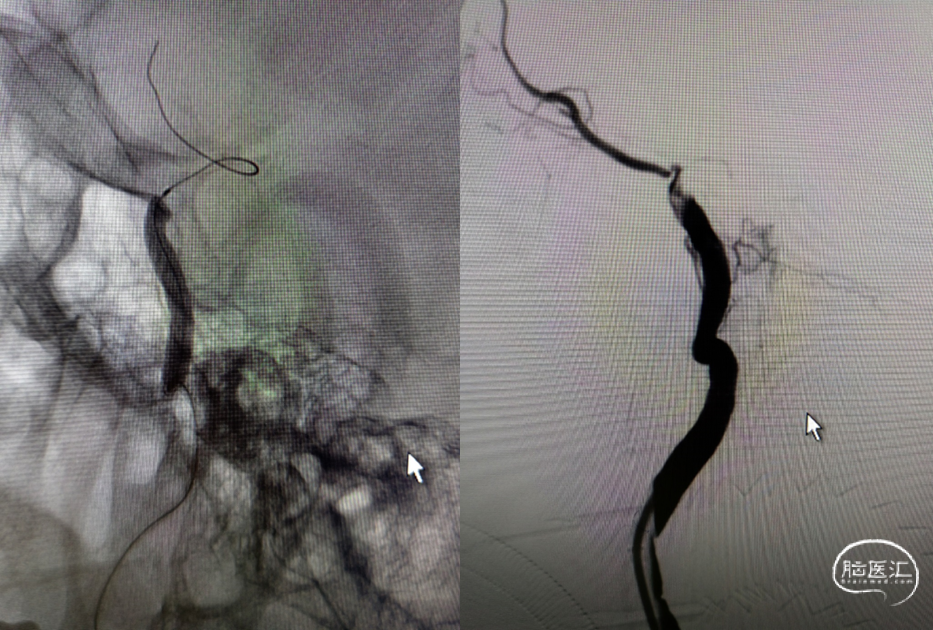

支架通过病变。

支架释放。

多次利用取栓支架SWIM技术对逃逸斑块进行取栓但未成功。

利用赛诺神畅 NOVA DES®颅内药物洗脱支架锚定后释放,血管再通,mTICI 3级,局部动脉给药替罗非班(0.2ug/kg.min)约3ml,持续15分钟。静脉(0.1ug/kg.min)持续泵入24小时后改为口服双抗。